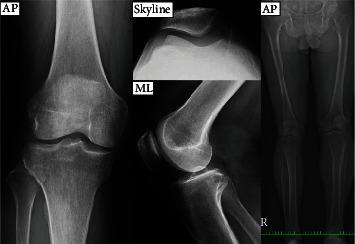

Mucoid degeneration of the anterior cruciate ligament (ACL) is a rare cause of anterior knee pain (AKP). Some case reports have been published; however, it is difficult to diagnose and is often underdiagnosed or misdiagnosed because of its pathophysiological ambiguity. We report a rare case of a patient diagnosed with bilateral mucoid degeneration of the ACL with AKP and no limited joint range of motion (ROM). A 59-year-old man with spontaneous right AKP was admitted to our hospital. He first underwent arthroscopic resection of the thickened medial plica protruding far into the medial patellofemoral joint (PFJ) but felt little effectiveness thereafter. He then had an arthroscopic release of the lateral patellar retinaculum because of valgus knee and patellar instability, which resulted in only temporary improvement. Then, the AKP relapsed, this time with limitations in the ROM. Magnetic resonance imaging (MRI0 showed a diffuse, thickened ACL with a high inhomogeneous intensity in the T2-weighted and proton density weighted images and which looked similar to a celery stalk. Based on the patient's history and MRI findings, we suspected mucoid degeneration of the ACL and subsequently performed arthroscopic excision. At the same time, AKP appeared on the other side. Since the MRI demonstrated a similar celery stalk image as before, the same operation was performed on this side, as well. Finally, AKP and the limitation of the ROM were relieved approximately one month after surgery. Due to the patient only suffering from AKP with a preserved ROM, it took about 14 months to diagnose this disease. It should, therefore, always be considered in cases of AKP alone.

前交叉韧带(ACL)黏液样变性是引起膝前痛(AKP)的罕见原因。已有一些病例报告发表;然而,由于其病理生理机制不明确,该病难以诊断,常被漏诊或误诊。我们报告一例罕见病例,患者被诊断为双侧ACL黏液样变性伴AKP,且关节活动范围(ROM)无受限。一名59岁男性因右膝自发AKP入院。他首先接受了关节镜下切除向内突出至内侧髌股关节(PFJ)的增厚内侧皱襞,但术后效果不佳。随后,由于膝外翻和髌骨不稳定,他又接受了关节镜下外侧髌支持带松解术,仅获得了短暂改善。之后,AKP复发,此次伴有ROM受限。磁共振成像(MRI)显示ACL弥漫性增厚,在T2加权像和质子密度加权像上呈不均匀高信号,类似芹菜茎。根据患者病史和MRI表现,我们怀疑为ACL黏液样变性,随后进行了关节镜下切除术。与此同时,另一侧也出现了AKP。由于MRI显示与之前类似的芹菜茎样图像,该侧也进行了相同手术。最后,术后约1个月AKP和ROM受限症状得到缓解。由于该患者仅患有AKP且ROM正常,诊断该病花费了约14个月时间。因此,对于仅表现为AKP的病例,应始终考虑该病。